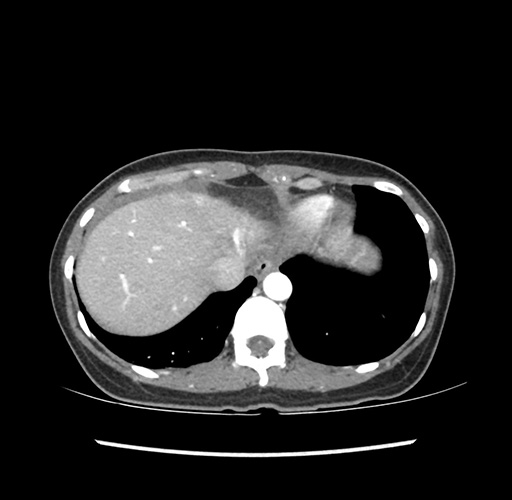

Imaging Analysis

Look through the patient's CT scan to identify any areas of concern for the necessary procedure.

Based on your CT findings, which issue(s) would give reason for "planned slowing down moment(s)" in this case?